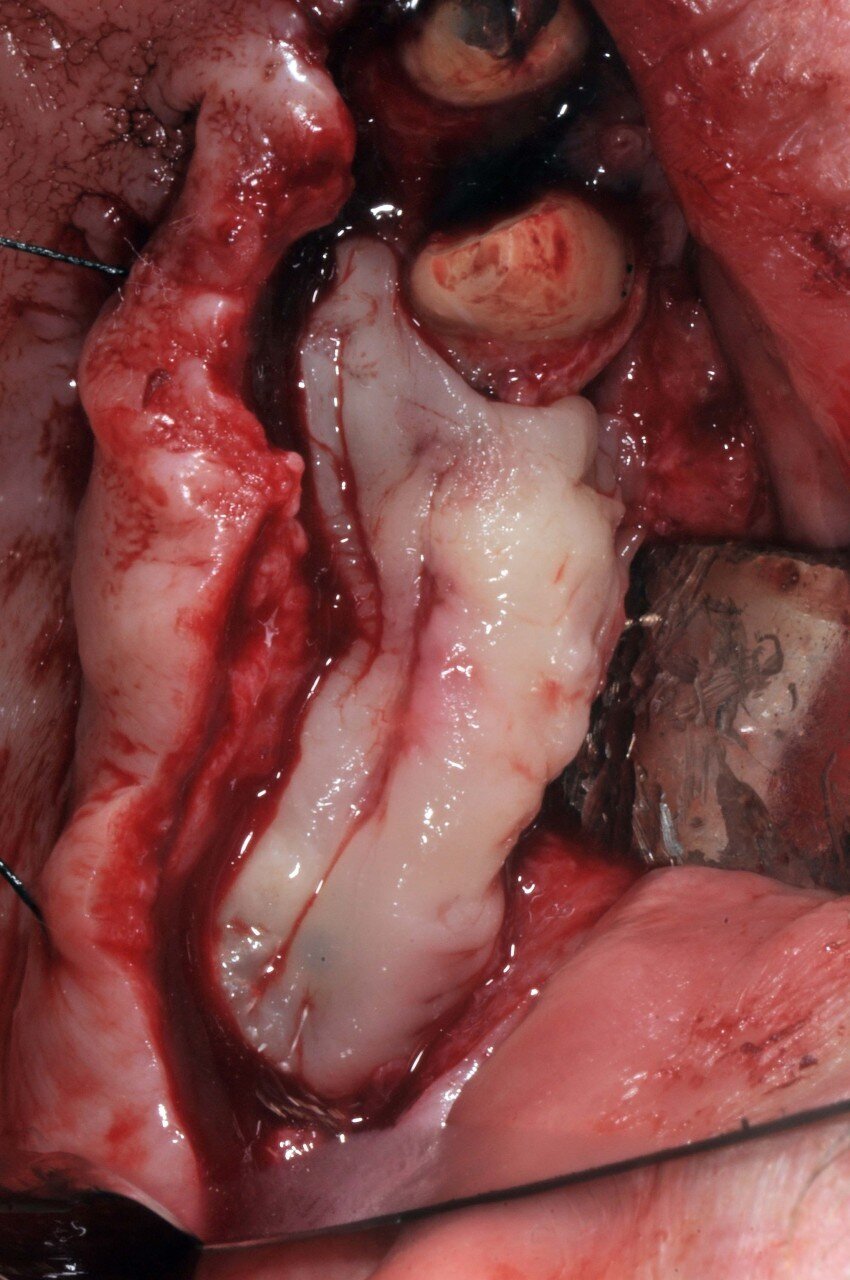

È stato eseguito un lembo a spessore totale senza tagli verticali di rilascio e una regolarizzazione della cresta ossea per mezzo di un raschietto per osso, che ha permesso di ottenere una quantità ulteriore di osso oltre a quello ottenuto per mezzo della fresatura a basso numero di giri secondo la procedura BTI. L’osso ottenuto è stato mischiato con gel piastrinico ottenuto mediante centrifugazione del sangue del paziente secondo la metodica PRGF Endoret ed inserito in parte all’interno dell’osteotomia del dente 26 a protezione della membrana sinusale e in parte protezione della parete ossea vestibolare del dente 24 che era particolarmente sottile. Dopo aver applicato i tappi di guarigione i lembi sono stati suturati per ottenere una guarigione sommersa (Figg. 5-7). Dopo quattro mesi di guarigione gli impianti furono scoperti e due pilastri Multi-im sono stati avvitati con i relativi tappi di guarigione.